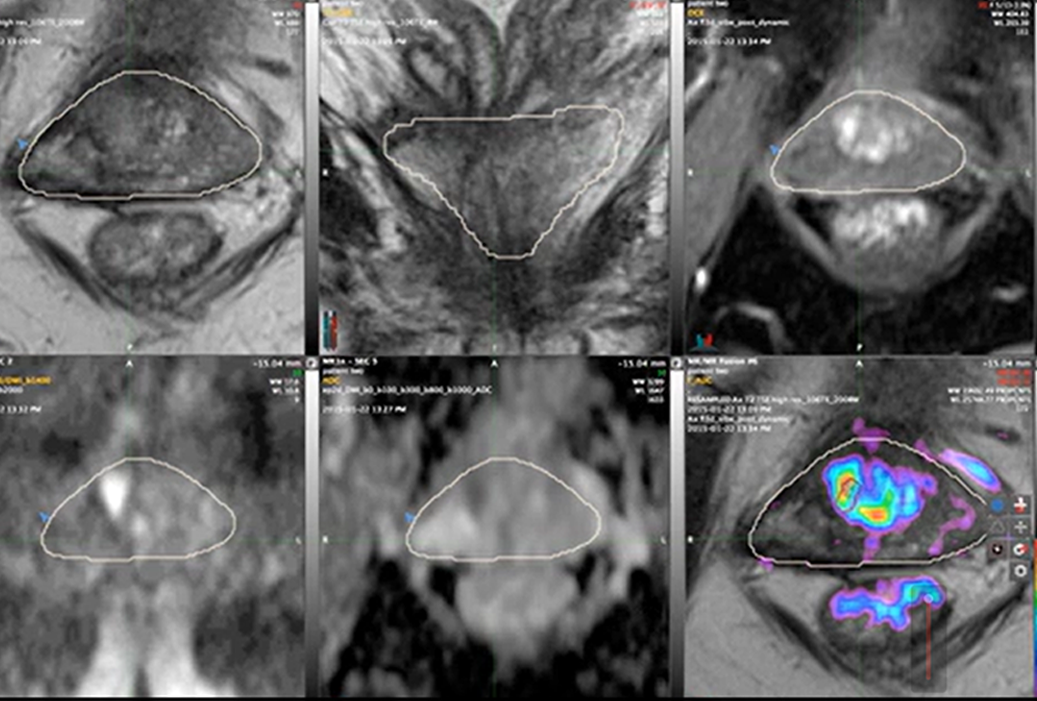

Multiparametric MRI Contouring: Six Views, One Volume

With PCL: Dr. Allen accesses six different MRI sequence views of the same anatomical plane - T2-weighted, ADC, diffusion, vascularity patterns - to contour lesions with millimeter precision.

Six different MRI sequences accessible for precision contouring - T2-weighted, ADC maps, diffusion, vascularity, and more

"The fusion software allows me to view the T2, the dynamically enhanced and the high B value scans, plus the ADC map simultaneously. I can contour the targets using whichever images best show the lesion."